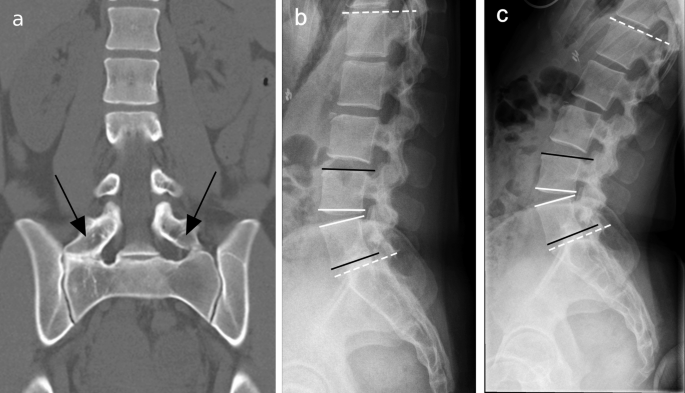

Conventionele röntgenfoto’s worden vaak gebruikt als eerste beeldvormende stap.

Kenmerken:

geschikt voor herkenning van vergrote dwarsuitsteeksels

beoordeling van contact of fusie met het sacrum

beperkte weergave van weke delen

Röntgenonderzoek kan een LSTV aantonen, maar mist detail en geeft geen informatie over mogelijke pijnbronnen.

Een belangrijk aandachtspunt bij LSTV’s is correcte nummering van de wervelkolom.

Door overgangsvariaties kan:

L5 worden aangezien voor S1

verwarring ontstaan over het exacte niveau

interpretatie van beeldvorming worden bemoeilijkt

Onjuiste nummering kan gevolgen hebben voor verdere diagnostiek en behandeling. Zorgvuldige beoordeling is daarom essentieel.